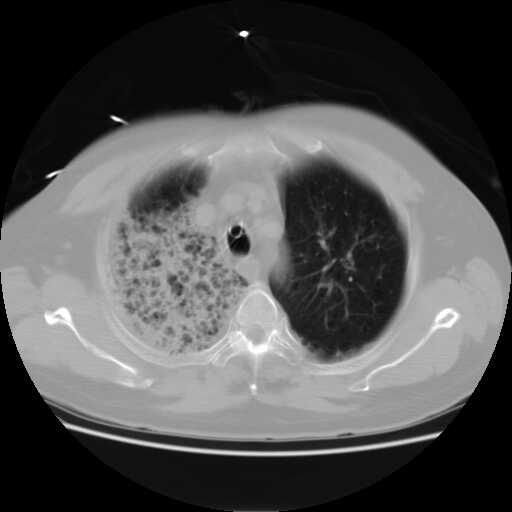

2008.8.17ct

病变从8.11-8.17明显改变,增多,以蜂窝状改变为主,类蜂窝肺,似弥漫性肺泡癌,但是病变进展太快,不符合弥漫性细支气管肺泡癌。因此考虑为特殊微生物感染,多以霉菌类常见,建议细菌微生物学检查。

疑点二:影象表现怪异,大片阴影内见多发筛孔征,如何解释.

结合临床慢支炎肺气肿,肺心病病史,三次胸片观察可见病情发展变化迅速,病情凶险,考虑多重感染伴ards.